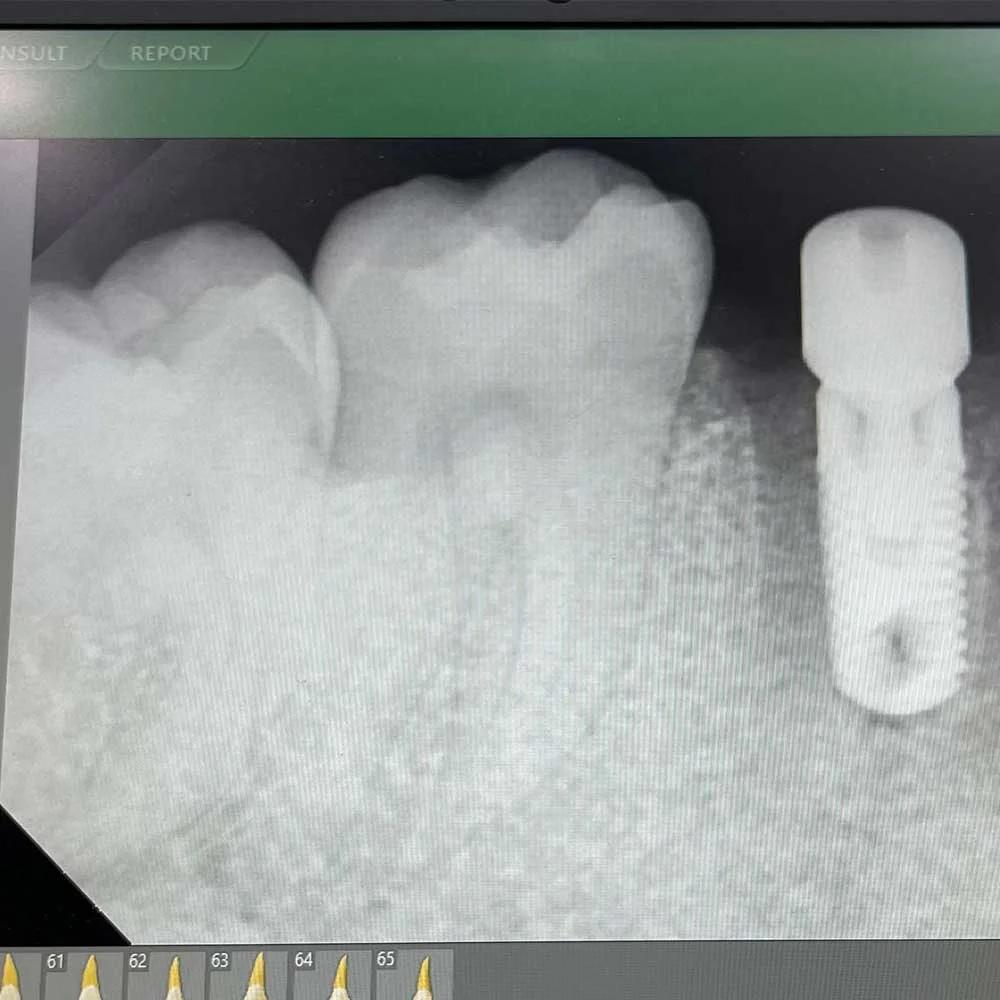

Dental implants are frames made of titanium and fitted into the Jawbone to fill the gap where the teeth were missing. Implants, unlike dentures, are similar to normal teeth, offering a secure base against which crowns, bridges, or full-arch restorations can be built. They not only prevent bone loss but also enable you to maintain your facial shape and enjoy your favourite food without pain.

1. Single Tooth Implants:Ideal when it comes to replacing a single lost tooth without affecting the neighbouring teeth.

2. High Technology: We utilise the best equipment to ensure accurate diagnostics and treatment.

Dental Implants